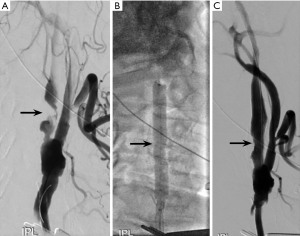

An 81-year-old male with a history of previous right CEA with Dacron patch, who developed 90% restenosis distal to the patch diagnosed based on carotid DUS (ICA PSV 230 cm/sec, ICA/CCA ratio of 1.7) and confirmed by a CTA of the head and neck. The stenosis has been progressing despite optimal medical treatment and was circumferentially calcified with a 4 mm thickness (Figure 4A). The patient’s cardiovascular risk factors included prior smoking, CAD, deep vein thrombosis, hypertension, and CKD stage 3a. The patient was counseled on the off-label use and was elected to proceed with a TCAR with shockwave lithotripsy angioplasty balloon. After the intraoperative angiogram demonstrated 90% stenosis of the right ICA (Figure 4A), the lesion was pre-dilated with a 7 mm × 6 cm shockwave lithotripsy angioplasty balloon (6 cycles; Figure 4B) with excellent luminal gain, followed by stenting with a 10 mm × 40 mm Precise stent (Figure 4C). Total flow reversal time was 22 minutes. At one-year follow-up, the patient remained neurologically intact, and the right ICA stent was widely patent on US (ICA/CCA Ratio of 1.7, ICA PSV 126 cm/sec).